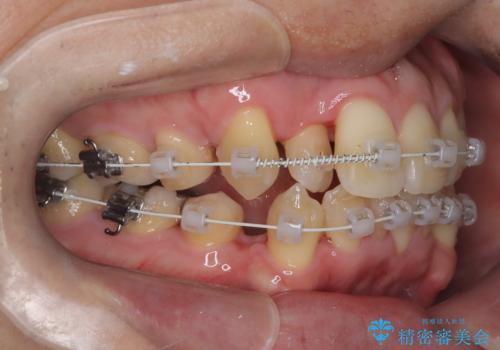

- ワイヤー(審美装置)

デコボコの量が多かったため上下左右4を抜歯してワイヤー矯正で治療を行いました。

スムーズに治療を進める事ができ、2年2か月で治療をお終えました。